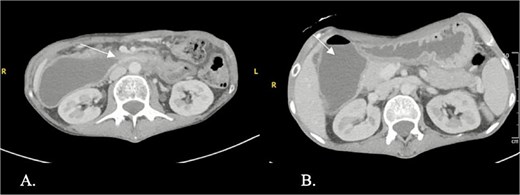

CT enterography demonstrated strictures involving the third and fourth portions of the duodenum with proximal gastric dilatation (Fig. 1), inflammatory changes in the transverse colon mesentery, and thickening of the neoterminal ileum (Fig. 2). Push enteroscopy confirmed a non-traversable stricture with multiple ulcers in the third portion of the duodenum; biopsies indicated chronic duodenitis. Colonoscopy revealed a non-traversable stricture at the ileocolic anastomosis, with biopsies showing severely active chronic enteritis (Fig. 3).

Axial contrast-enhanced computed tomography (CT) showing a stricture with thickening in the third and fourth parts of the duodenum (arrow) and proximal duodenal and gastric dilatation.